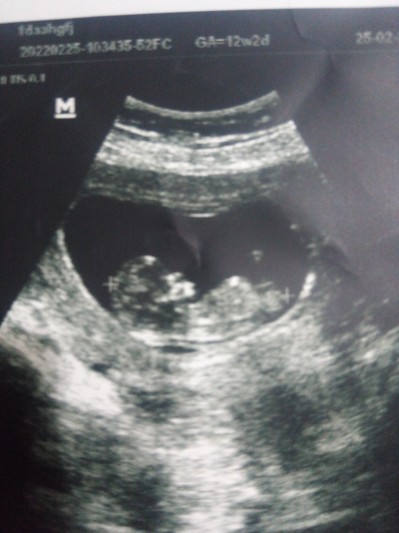

Anlayanlar bakabilirmi:)

image

İçime erkek doğdu

Ben kıza benzettim canım

Kız bence ılk bebek mı